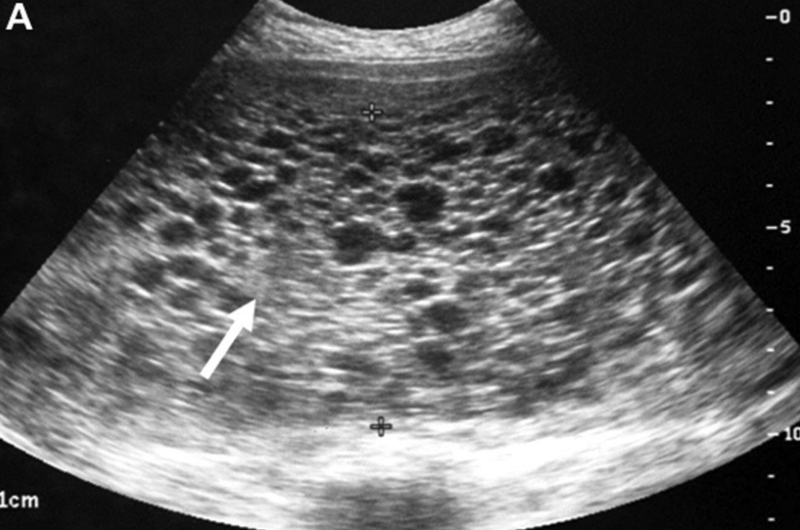

Hình ảnh siêu âm cho thấy giun chui ống mật, cụ thể là đường mật bị giãn rộng và hình trong ống mật chủ tập trung nhiều hình ảnh tăng âm theo một vệt dài (con giun).